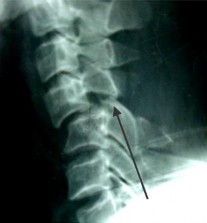

SAU MỔ: C5-C6 đã được nắn chỉnh. KHX Bohlman cải tiến.

THẲNG NGHIÊNG